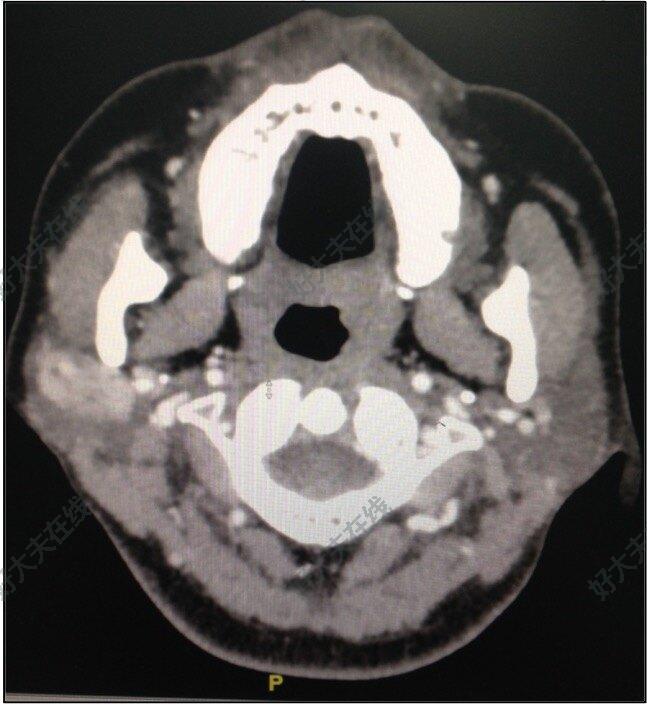

下頜下腺腫瘤的傳統(tǒng)治療下頜下腺腫瘤是口腔頜面外科的常見病和多發(fā)病,多為良性腫瘤,表現(xiàn)為生長緩慢的無痛性腫塊,常于無意中發(fā)現(xiàn),活動,無粘連,無功能障礙,表面光滑或呈結(jié)節(jié)狀,治療以手術(shù)為主。傳統(tǒng)下頜下腺手術(shù)切口設(shè)計(jì)位于下頜骨下緣下1.5~2cm,長度約6cm,該入路直接,顯露充分,操作方便,但有損傷面神經(jīng)下頜緣支風(fēng)險(xiǎn),導(dǎo)致口角歪斜,術(shù)后面部瘢痕明顯,嚴(yán)重影響美觀及生活質(zhì)量。即使將切口設(shè)計(jì)在皮紋內(nèi),以美容線精細(xì)縫合,仍會留有瘢痕。隨著對面頸部手術(shù)美容要求的提高,許多年輕患者和特殊職業(yè)人群,不能接受面頸部手術(shù)瘢痕。那么有沒有方法能解決上述問題,在保證安全有效切除腫瘤的同時,又能達(dá)到微創(chuàng)美觀甚至無痕的效果,做到“魚與熊掌兼得”?下頜下腺手術(shù)新思路北京大學(xué)口腔醫(yī)院口腔頜面外科三病區(qū)團(tuán)隊(duì)參考經(jīng)口內(nèi)鏡甲狀腺手術(shù),在合理把握手術(shù)適應(yīng)證的前提下,積極探索面頸部無痕手術(shù),并順利開展完成內(nèi)鏡輔助經(jīng)口底及前庭溝下頜下腺腫瘤切除,避免了頜下皮膚切口,做到了完全無痕的效果,且無面神經(jīng)損傷風(fēng)險(xiǎn)?;颊呒凹覍賹Υ朔N手術(shù)方式起初具有一些疑問:這種手術(shù)能做到既能切除腫瘤,又能不留疤痕嗎?手術(shù)對進(jìn)食是否有影響?經(jīng)過醫(yī)師們的耐心講解,患者和家屬解除了顧慮,欣然接受了這種創(chuàng)新式手術(shù)治療。手術(shù)將患者頸部的切口隱藏在口腔內(nèi),術(shù)后六個小時患者可以吃一些質(zhì)地柔軟的食物,僅需注意口腔衛(wèi)生即可,并不影響正常的口腔咀嚼和吞咽功能,術(shù)后第二天便可出院。內(nèi)鏡輔助的優(yōu)勢與不足內(nèi)鏡輔助下經(jīng)口下頜下腺腫瘤切除具有以下優(yōu)勢:①面頸部完全無痕,不影響美觀;②避開面神經(jīng)下頜緣支,無面癱風(fēng)險(xiǎn);③?不需結(jié)扎主干血管,保全組織結(jié)構(gòu),損傷小;④內(nèi)鏡下操作視野清晰。但也存在不足,如手術(shù)操作空間狹小、對術(shù)者經(jīng)驗(yàn)和操作技能要求高、學(xué)習(xí)曲線長等。雖處于探索階段,但北京大學(xué)口腔醫(yī)院口腔頜面外科三病區(qū)團(tuán)隊(duì)始終秉承“厚德尚學(xué)、精醫(yī)濟(jì)世”的院訓(xùn),努力追求唾液腺腫瘤手術(shù)微創(chuàng)無痕化,提高手術(shù)質(zhì)量,造?;颊撸嬲_(dá)到“病從口出,刀過無痕”。圖1~圖6展示了一例下頜下腺混合瘤切除術(shù)。病例展示圖1患者女,右側(cè)下頜下腺腫瘤八年圖2?增強(qiáng)CT顯示患者右側(cè)下頜下腺內(nèi)存在大小約2.3×2.5cm腫物圖3設(shè)計(jì)口底手術(shù)入路圖4?內(nèi)鏡輔助下,結(jié)扎面動脈至下頜下腺分支圖5?完整摘除腫瘤及腺體圖6?術(shù)后患者頸部完全無痕